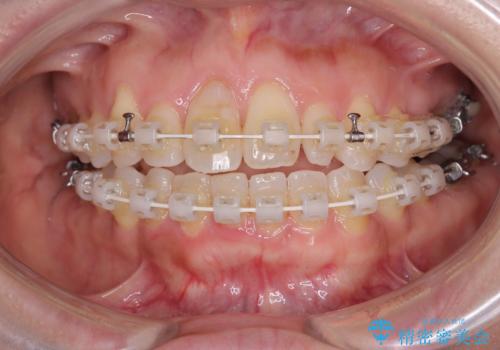

- 審美装置

- 2年1ヶ月

予想通り左側の咬み合わせの調整に苦労をしましたが、最終的には違和感のない咬み合わせを達成することができました。